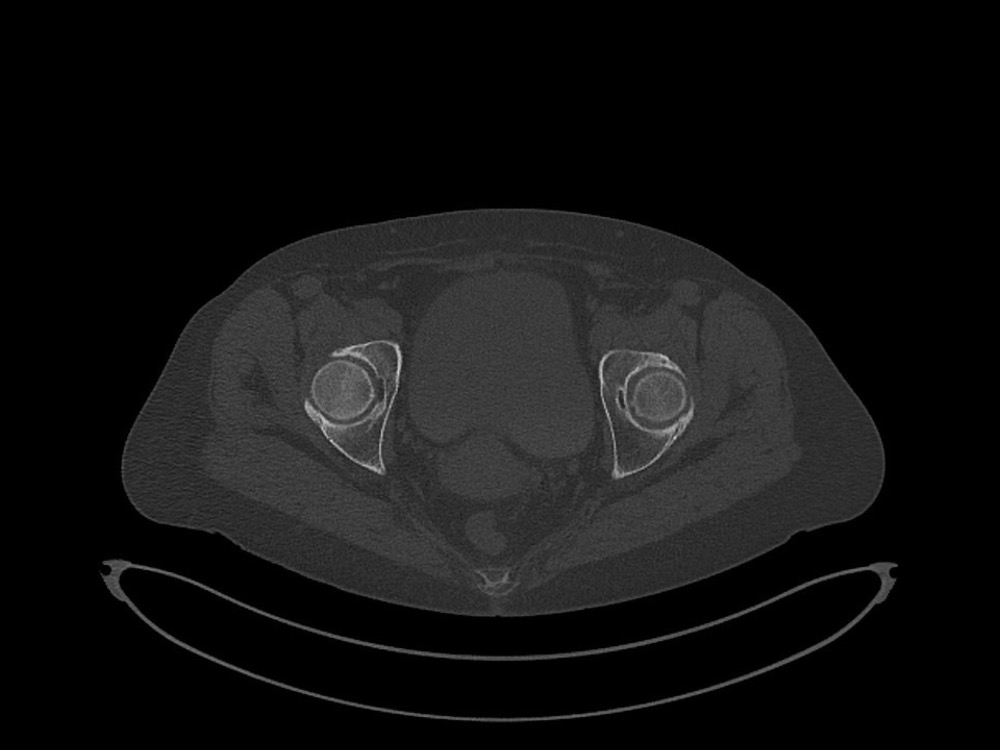

Douleurs de hanche

Linda Ouerd 06/11/2019